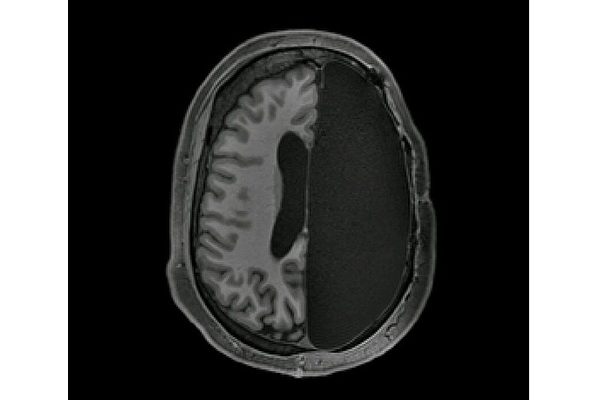

本周发表于《细胞研究》(Cell

Reports)期刊上的一份论文,研究了六名只有半个大脑患者的神经网络工作机

本月发表在《细胞》期刊上的一篇报告揭示,一位因患肿瘤而右边大脑被切掉三分之一的男孩,在手术三年后竟然